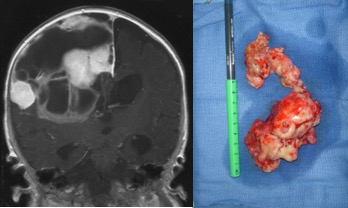

macroscopiquement, la tumeur a le plus souvent une attache méningée, et elle est d’emblée apparente à l’ouverture durale. elle est de consistance ferme, avec un fort contingent kystique ; elle se clive relativement bien des structures cérébrales et vasculaires adjacentes. lors des récidives cependant, elle peut adhérer intimement aux vaisseaux du polygone de willis et infiltrer le cortex et les ventricules.

c’est en règle générale une très volumineuse tumeur chez un très jeune nourrisson, souvent même un nouveau-né. il peut exister des métastases d’emblée.